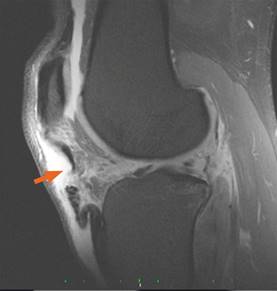

En los controles radiográficos y tomográficos se diagnosticó fractura de las apófisis transversas del lado izquierdo de T10, T11, L3 y L4, fracturas de los trayectos posteriores de los arcos costales izquierdos 7o, 8o, 10o y 11o, fracturas por compresión de T8, T9 y T10 del 10%. La tomografía computarizada (TC) de la rodilla izquierda arrojó el diagnóstico de fractura en el platillo tibial posterolateral de la meseta tibial, no desplazada (hundimiento menor de dos milímetros). Se complementó con una resonancia magnética (IRM) de la rodilla izquierda, que mostró desgarro del cuerno posterior del menisco medial, fractura compleja del cuerno posterior del menisco lateral, ruptura completa del tendón patelar, con separación de los extremos de 2.4 cm (Figura 1); ruptura completa del LCM, ruptura completa del LCA (Figura 2), derrame articular, signos de ruptura de la cápsula articular en su porción posteromedial, condromalacia patelar grado II con datos de fracturas condrales en el vértice posterior y faceta lateral de la rótula, contusión ósea y fractura subcondral y trabecular de la meseta lateral de la tibia y lesión grado I del LCL.

Figura 1: Resonancia magnética (IRM), corte sagital T2 FAT-SAT; muestra interrupción en la intensidad de la señal a nivel del TP, compatible con ruptura completa.